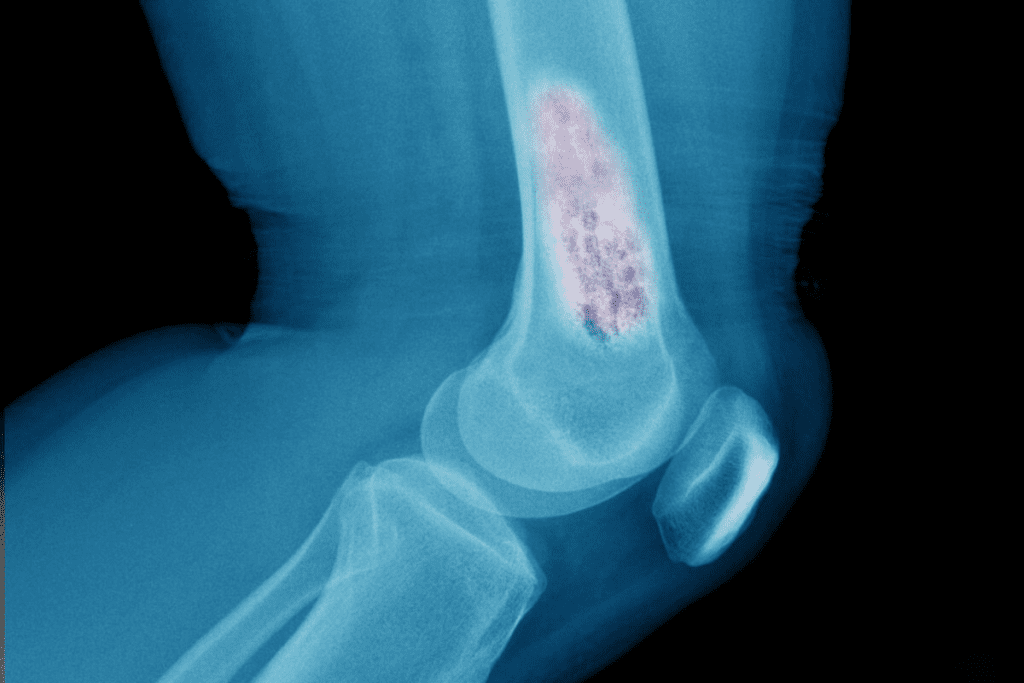

What Does a Bone Scan Show? Detecting Abnormalities

Normal vs. Abnormal Bone Scan Results

Bone scan results can be normal or abnormal. Normal results mean the radiotracer spreads evenly in the bones. Abnormal results show uneven radiotracer uptake, pointing to different conditions.

Abnormal results can mean many things, like fractures, infections, or cancer. But, not all abnormal results are cancer. They can also show other bone issues.

Hot Spots and Cold Spots: What They Indicate

Bone scans show “hot spots” and “cold spots.” Hot spots mean more radiotracer, showing active bone areas. This could be due to fractures, infections, or tumors. Cold spots have less radiotracer, suggesting issues like avascular necrosis or bone lesions.

Bone Scans in Cancer Detection and Staging

Bone scans are key in finding cancer and seeing how far it has spread to bones. They help spot both bone cancers and cancer that has spread to bones. This info is vital for planning treatment.

Primary Bone Cancers Visible on Scans

Bone scans can find different types of bone cancers. These include osteosarcoma, Ewing’s sarcoma, and chondrosarcoma. They work because these cancers use a lot of energy, showing up on scans.

Patterns of Cancer Presentation on Bone Scans

Cancer can show up in different ways on bone scans. It might look like hot spots, spread out, or even cold spots. The way it looks can tell doctors a lot about the cancer.